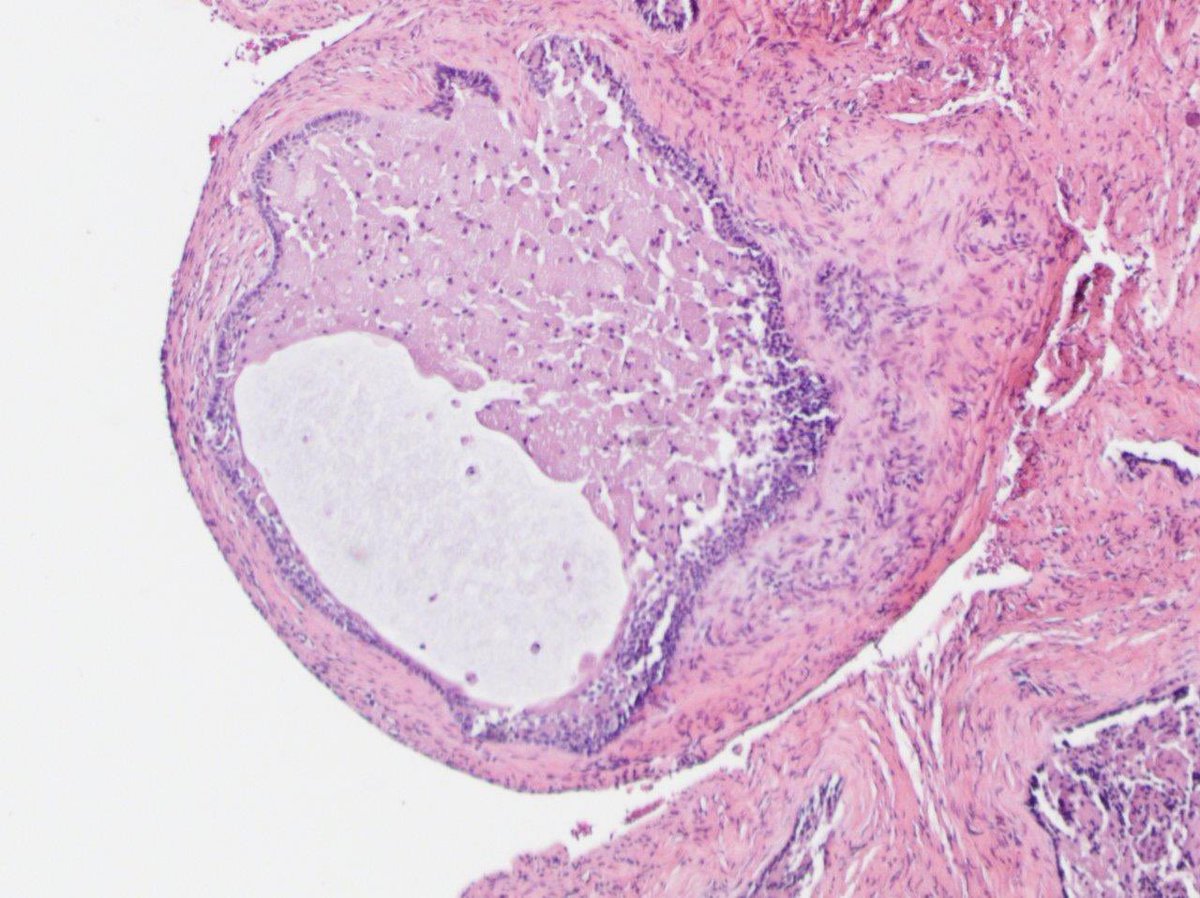

Multilocular lucency posterior mandible curettage. This is an example of the rare granular cell variant of ameloblastoma. The stellate reticulum is replaced by granular cells full of lysosomes (CD68+ S100-) #PathTwitter #OralPath